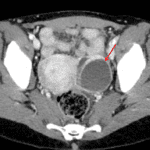

Indication: Right lower quadrant pain

- Fluid-filled serpiginous tubular structure which extends from the right adnexa along the anterior and superior margins of the uterine fundus with mural hyperenhancement and surrounding fat stranding

- Peripherally-enhancing, low attenuation structure in the left ovary measuring 5 x 4 cm

- Small volume free intraperitoneal fluid layering in the anatomic pelvis

- Pyosalpinx

Findings compatible with right hydrosalpinx and possible pyosalpinx given surrounding inflammatory changes. Recommend pelvic ultrasound for further evaluation.

Fluid-attenuation structure in the left ovary, which can also be further evaluated by pelvic ultrasound.

Mild dilation and mural thickening of several loops of small bowel in the pelvis is likely reactive to the above described process.